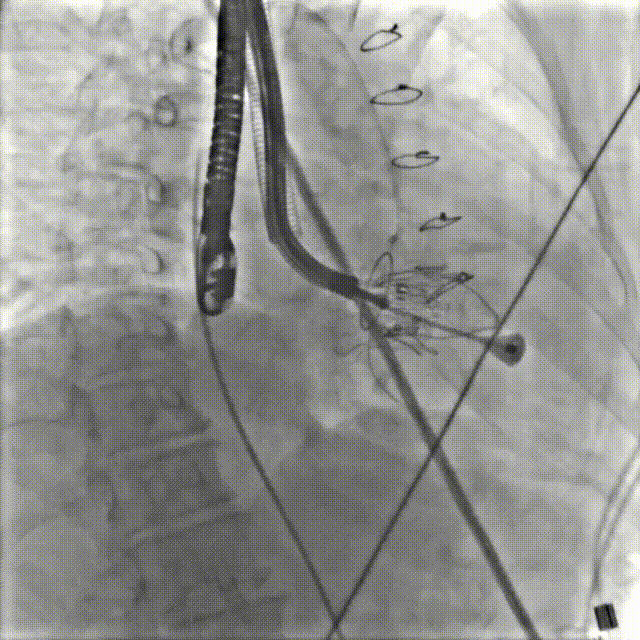

术前造影

图片

术中造影

术后造影